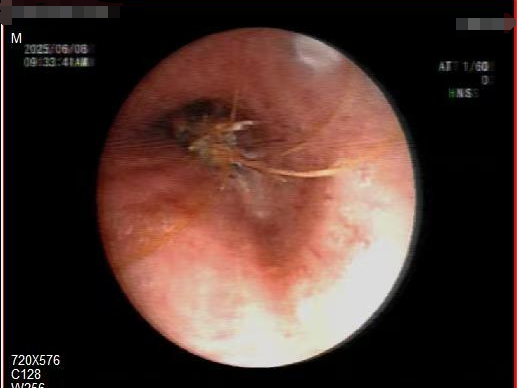

呼吸与危重症医学科副主任李涛立即安排支气管镜检查,在纤细的镜管探入下,只见那只虾顽固地嵌在支气管管口,周围黏膜已微微红肿。李涛屏息凝神,用微型钳子轻柔夹取至咽喉部,这只“误入歧途”的河虾经杨先生口中咳出。

气管镜是一种带有光源和摄像头的细长管道,通过鼻腔或口腔进入气道,医生可直观观察气管、支气管内的异物,并通过器械将其取出。